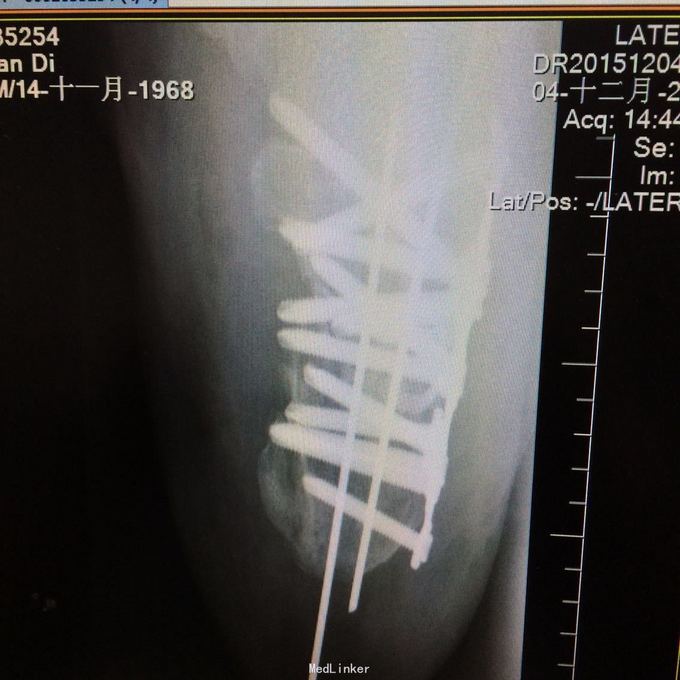

1、左肱骨远端粉碎性开放性骨折;2、左肘关节半脱位;3、左手第4、5掌骨远端骨折;4、右手第1、3、4远节指骨骨折;5、右手第5中节、远节指骨骨折;6、鼻部软组织挫裂伤;鼻中隔骨折;7、右侧第3--7肋骨折;8、左跟骨粉碎性骨折;9、左眉弓软质挫裂伤;10、左肺挫伤;11、脑震荡。 1.完善三大常规、PT四项、生化等各项常规检查; 2.完善CT检查,予抗破伤风、抗感染、镇痛、止血等对症支持治疗; 3.请口腔、耳鼻喉、眼科等相关科室会诊; 4.请示上级医师,指导下步治疗。 手术时间:2015年11月15日 术后诊断:左肱骨远端开放性粉碎性骨折 麻醉方式:全身麻醉 手术名称:左肱骨远端开放性粉碎性骨折清创缝合外固定架固定术 手术时间:2015年12月25日 术后诊断:左肱骨远端粉碎性骨折 麻醉方式:臂丛麻醉 手术名称:左肱骨远端粉碎性骨折切开复位内固定术 。 手术时间:2015-12-3 术后诊断:左跟骨粉碎性骨折;左肱骨远端粉碎性开放性骨折;左肘关节半脱位;左手第4、5掌骨远端骨折;右手第1、3、4远节指骨骨折;右手第5中节、远节指骨骨折;右足拇趾撕脱骨折并趾间关节脱位;鼻部软组织挫裂伤;鼻中隔骨折;右侧第3--7肋骨折;左眉弓挫裂伤;左肺挫伤;脑震荡。 麻醉方式:腰硬联合 手术名称:左跟骨粉碎性骨折切开复位钛板内固定术